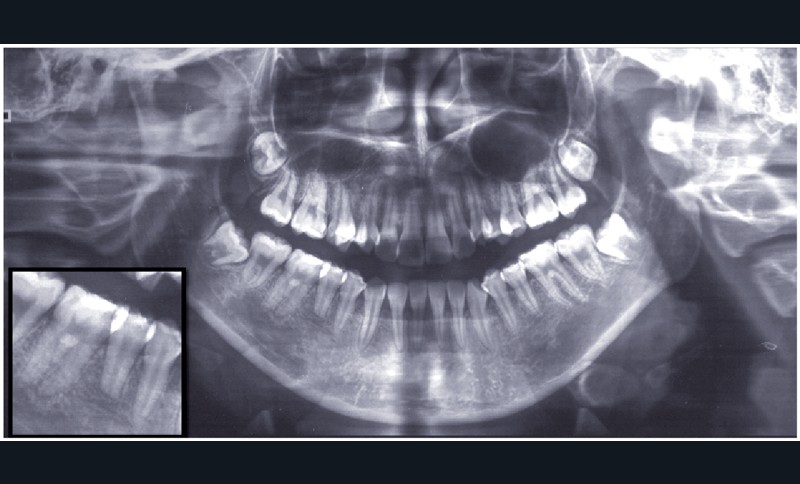

Diagnostic (fig. 1 à 3)

La classe III d’Angle et l’occlusion inversée s’accompagnent de signes de compensations alvéolo-dentaires : vestibuloversion des incisives supérieures (I/SN 114°) et linguoversion des incisives inférieures (IMPA 86°). L’encombrement à l’arcade maxillaire est important, souligné par des canines en infra-mésio-vestibulo-position.

Le choix du plan de traitement s’est porté sur un traitement chirurgico-orthodontique avec réalisation d’une classe II thérapeutique afin de limiter les déplacements dentaires à l’arcade mandibulaire suite au dépistage de rhizalyses idiopathiques sur les prémolaires inférieures (fig. 3) et de l’absence d’encombrement.